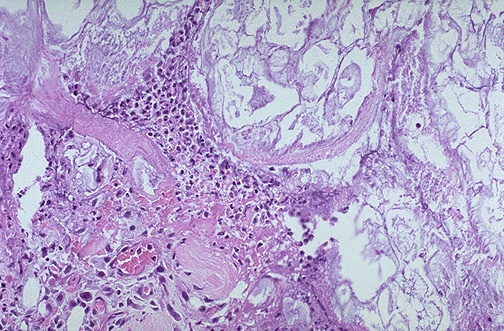

| Microscopically, acute pancreatitis has necrosis of pancreatic parenchyma (lower left) with acute inflammation and fat necrosis (right and upper part of photograph). Fat necrosis appears grossly as tan-yellow flecks of soft material within and on the surface of pancreas as well as on mesentery. |